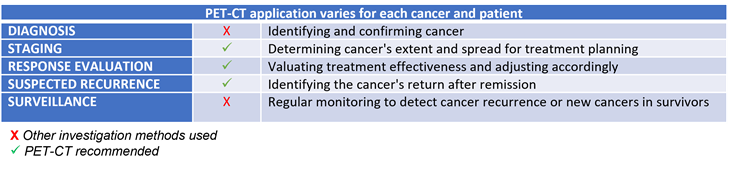

When are PET-CT scans used?

PET-CT scans are commonly used for, but not limited to: